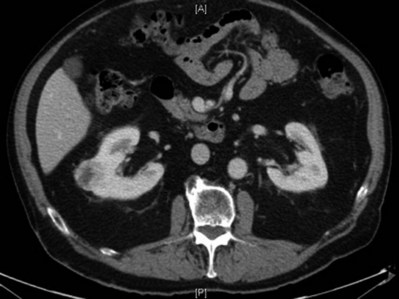

In addition to causing pain, cysts may compress the renal parenchyma or other adjacent organs, cause ureteral obstruction and obstructive uropathy, spontaneously bleed, cause hypertension, or become infected. Laparoscopic decortication or unroofing may be used to treat these cysts, which are typically simple in character (Fig. 55–22). Cysts with complex appearance, such as thickened septa, calcification, or enhancement (Bosniak class III-IV), may be explored and sampled laparoscopically to rule out renal cell carcinoma due to their increased risk of harboring malignancy (Cloix et al, 1996; Santiago et al, 1998). Options include cryoablation, enucleation, partial nephrectomy, or radical nephrectomy. If there is any question of cyst proximity to the collecting system, cystoscopy and placement of an open-ended ureteral catheter may be performed to ensure the integrity of the collecting system after cyst excision.

Figure 55–22 Axial CT scan in delayed phase after IV contrast administration, demonstrating peripelvic cysts in a patient who presented with left flank pain.